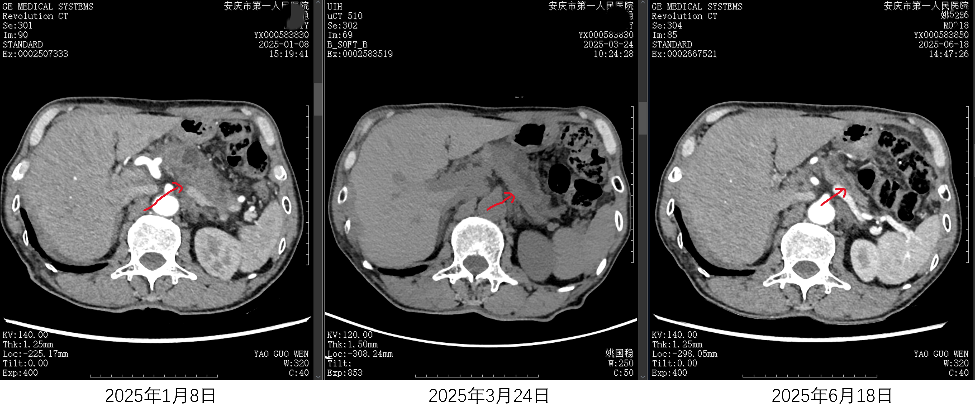

江昊副主任医师、甘盼盼医师与个案管理师团队,对姚老的病情、身体和心理状况进行了全面评估,制定了包含规范营养支持、症状监管、积极心理干预等多维度、多专业深化协作的个体化抗肿瘤治疗方案。经过半年的系统管理,姚老的肿瘤病灶近完全缓解,营养状况改善,血白蛋白指标和肿瘤标志物恢复正常水平,疼痛和焦虑情绪消失,治疗期间耐受性良好,无严重不良反应和治疗中断。目前,姚老仍在医院接受维持治疗,病情控制稳定,营养状况持续改善。

随着治疗,肿瘤(红色箭头所指处)大小在逐渐缩小